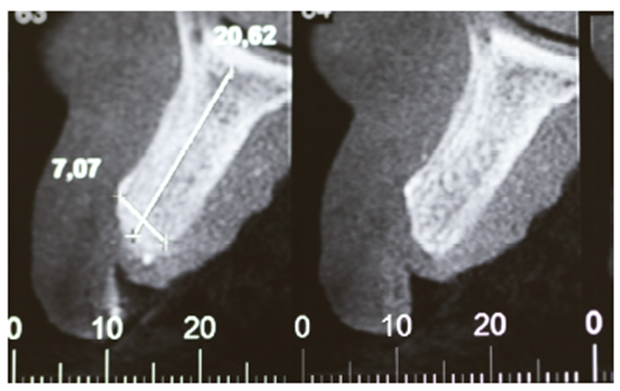

Foi solicitada a tomografia computadorizada total de maxila, com medidas de altura e espessura para planejamento cirúrgico.

Observou-se extenso defeito ósseo nos sentidos horizontais e verticais em pré-maxila (Figuras 2 e 3), sendo necessária a realização de uma extensa regeneração óssea guiada, com enxerto ósseo particulado (Geistlich – Bio-Oss), membrana de PTFE-d com reforço de titânio e membranas de fibrina autógena (LPRF).

Cinco meses após a remoção da membrana, foi realizada nova tomografia computadorizada com medidas de altura e espessura para planejamento dos implantes dentários, mostrando o sucesso obtido através da técnica de enxertia óssea com a membrana de PTFE-d (Figuras 14 e 15).